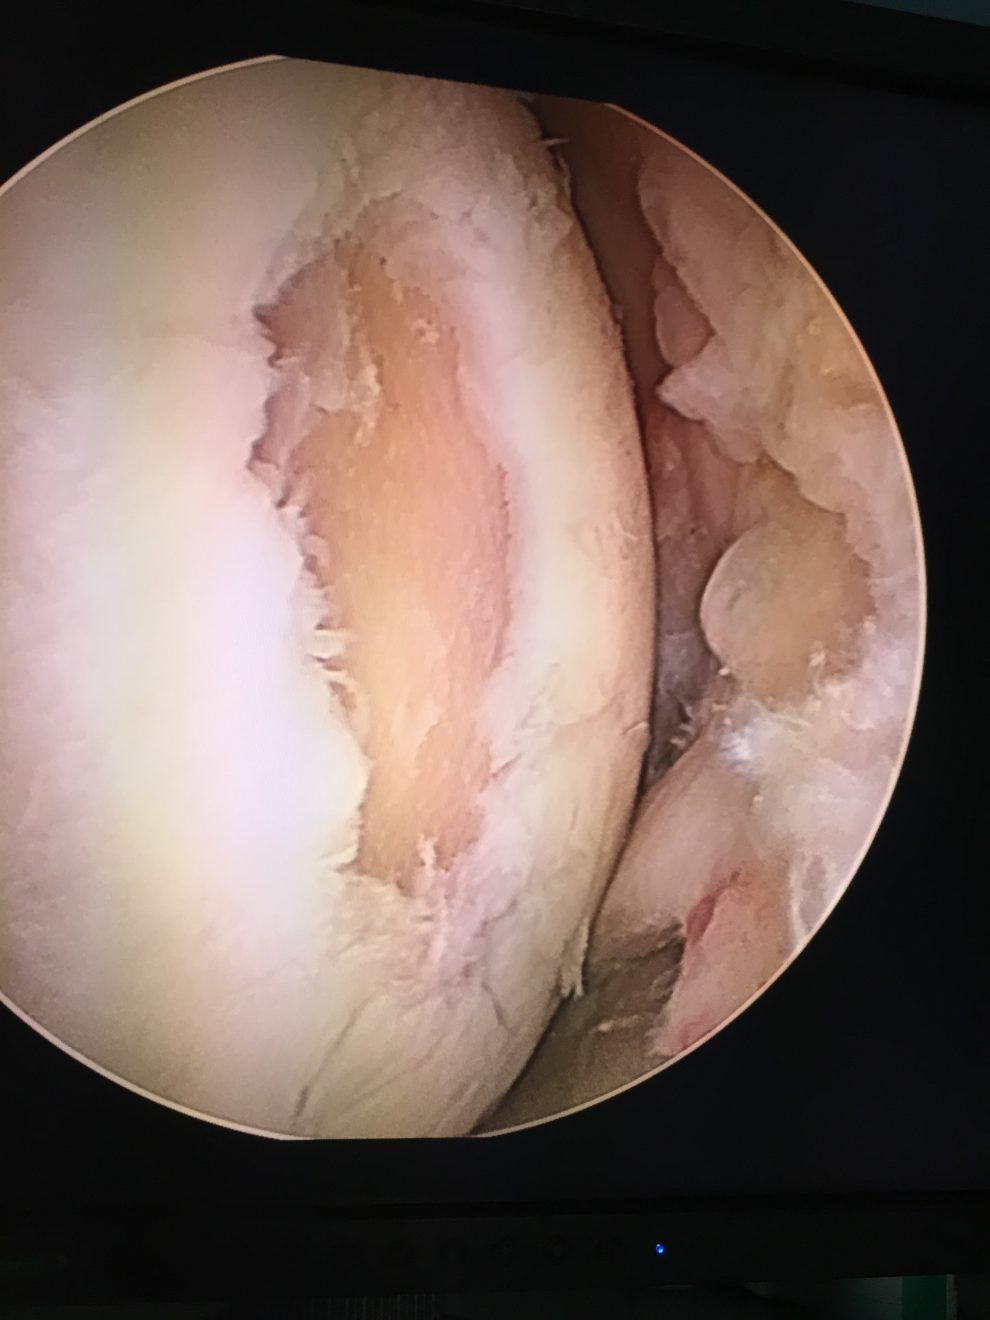

- wykonać zabieg artroskopii stawu. Możemy poddać leczeniu praktycznie wszystkie elementy stawu kolanowego, naprawiając łąkotkę, stymulować chrząstkę do naprawy, rekonstruować więzadła. Choć chrząstka szklista w stawie nie regeneruje się do nowej chrząstki, poprzez wykonanie zabiegów naprawczych, które polegają na oczyszczeniu uszkodzonej powierzchni chrzęstnej, a następnie wykonaniu mikrozłamań, nawierceń lub implantacji specjalnych węglowych pinów, aktywizujemy komórki szpiku (komórki mezenchymalne), które mają bardzo duży potencjał biologiczny. Pokrywają one uszkodzoną powierzchnię chrzęstną i wypełniają ubytek tkanką chrzęstną włóknistą, która nie jest chrząstką szklistą, ale bardzo ją przypomina. Zabieg ten uwalnia pacjenta od bólu i poprawia jakość jego życia.

Obrazy z artroskopii stawu